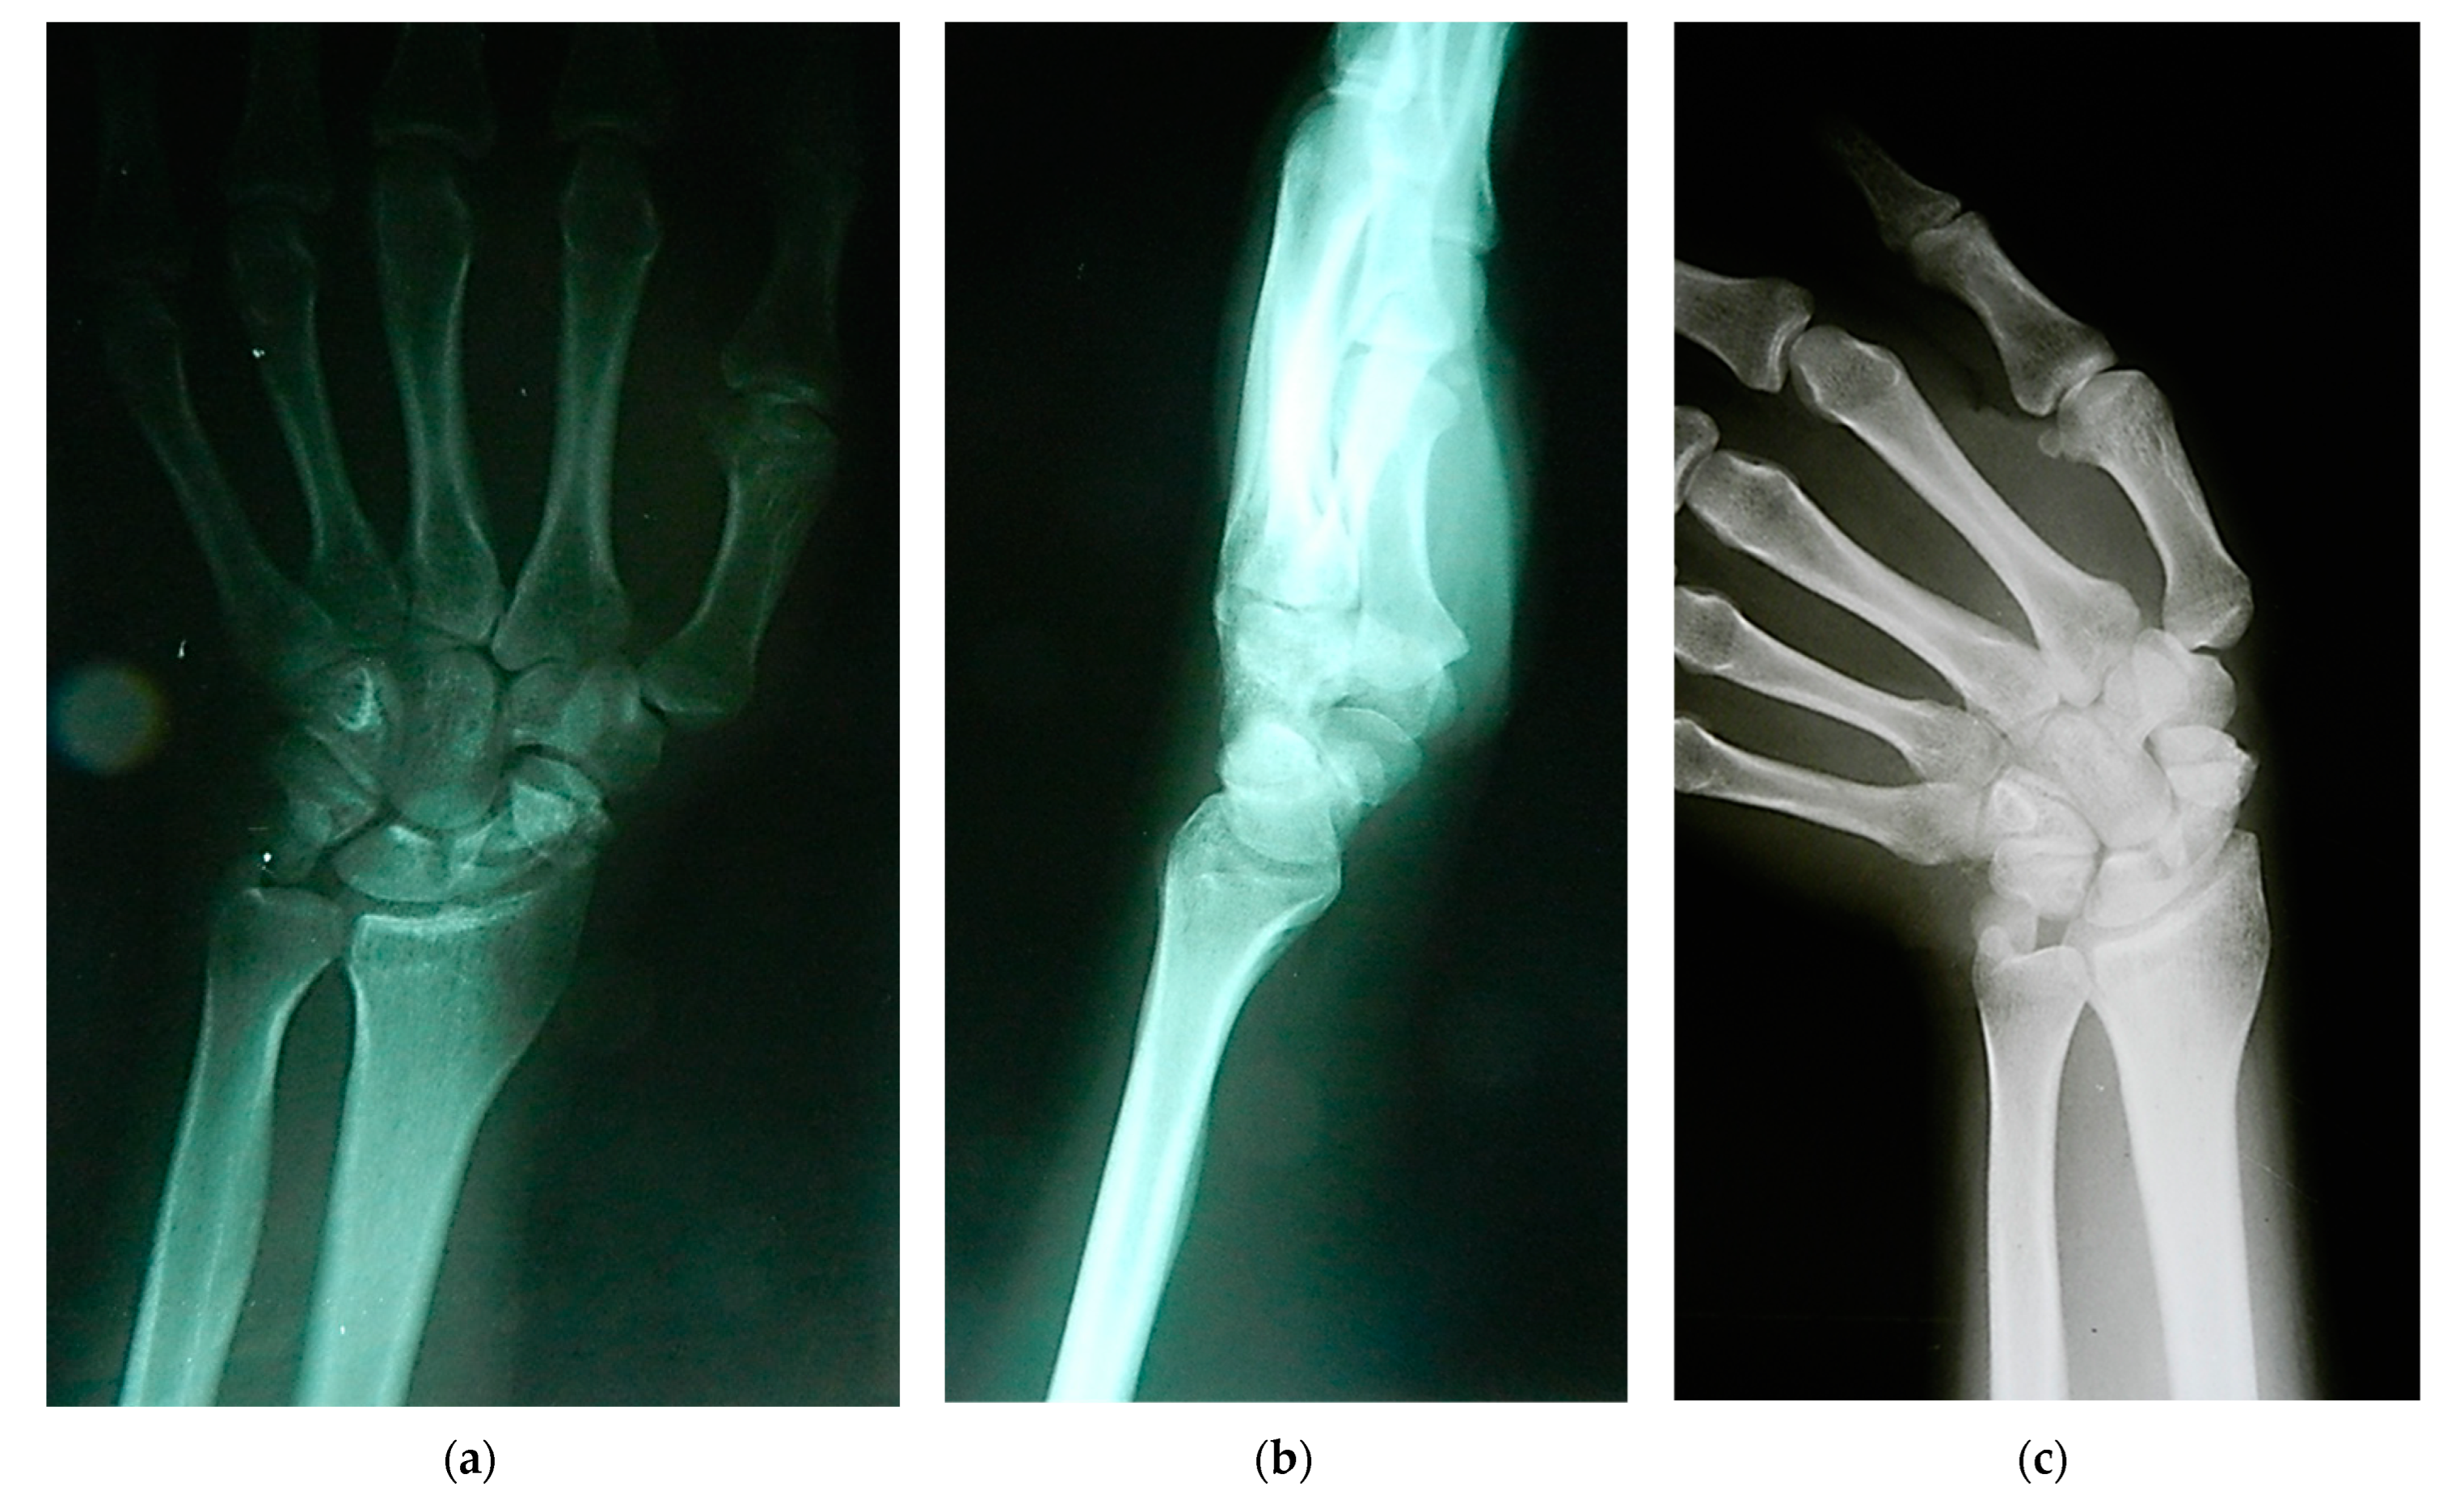

Scaphoid nonunion was defined as the absence of bony bridging the fracture for at least 6 months after the injury. The clinical diagnosis was confirmed by posteroanterior, lateral, and scaphoid radiographic views (Figure 2), whereas avascular necrosis of the scaphoid segment was diagnosed by contrast-enhanced MRI and confirmed intraoperatively by the lack of punctate bleeding at the fracture line.

Figure 2. Radiographs showing scaphoid nonunion: (a) posteroanterior; (b) lateral; and (c) scaphoid radiographic views.